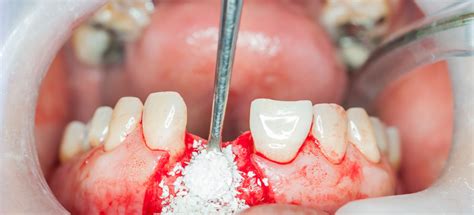

Un injerto de hueso dental es un procedimiento quirúrgico que consiste en implantar un fragmento óseo en el maxilar o la mandíbula con el objetivo de aumentar su volumen. De este modo, se incrementa la cantidad de hueso y se consolida el soporte necesario para la posterior colocación de un implante dental.

Si bien gozan de alta evidencia científica y son muy predecibles a medio y largo plazo, los injertos óseos requieren conocimiento especializado y experiencia por parte del cirujano bucal.